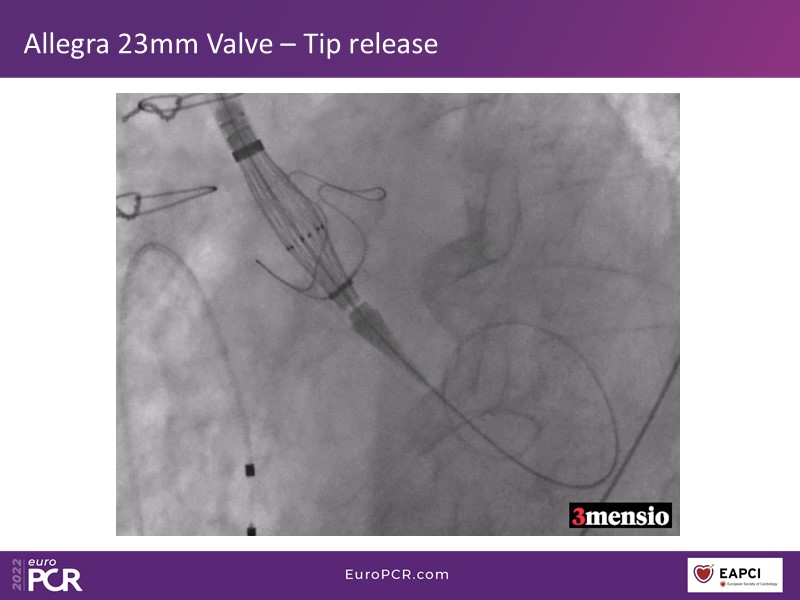

Through the presentation of real-life clinical cases, this session will allow you to discover the use of ALLEGRA for valve-in-valve TAVI, understand the management of coronary artery disease in TAVI patients, better detect when and how to protect coronary arteries during TAVI, or even learn how to perform commissural alignment with ALLEGRA.

- To discover how to use the ALLEGRA for valve-in-valve TAVI